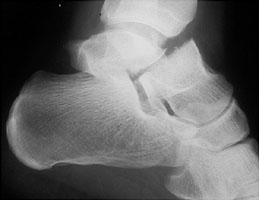

A | Lateral radiograph of the ankle. This shows a displaced fracture of the talar neck. |